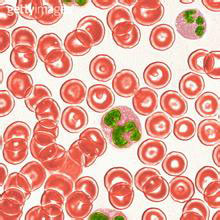

特发性血小板减少性紫癜

疾病介绍:特发性血小板减少性紫癜(ITP)亦称原发性或免疫性血小板减少性紫癜,其特点是外周血小板显著减少,骨髓巨核细胞发育成熟障碍,临床以皮肤黏膜或内脏出…【详细】